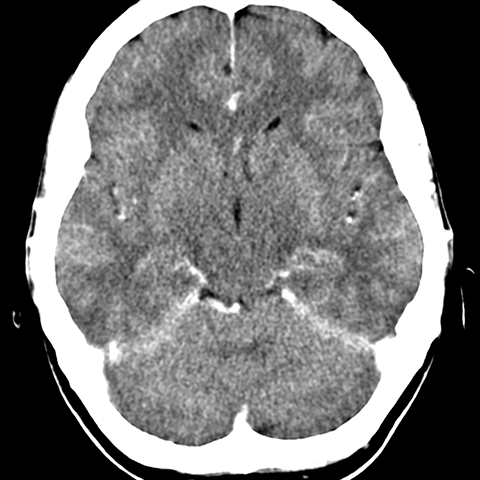

Frontal and temporal lobes, CT [3 of 6]